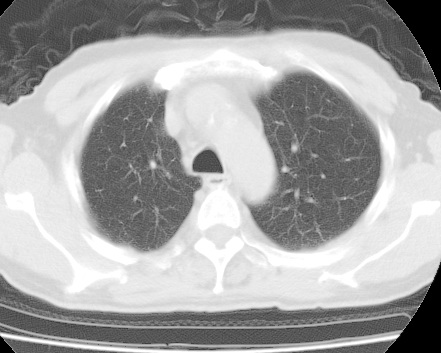

标题: CT24032:男65岁,咳嗽,吸烟20余年,无发热,咳痰 [打印本页]

标题: CT24032:男65岁,咳嗽,吸烟20余年,无发热,咳痰

考虑右肺中叶不张,请大家发表意见

右肺中叶不张、肺门轮廓增大,占位不除外;建议增强,必要时支气管镜详查。

右肺中叶不张,中叶支气管开口不清,建议支气管镜检查。

右肺中叶支气管闭塞,中叶肺不张,右侧肺门见肿块影。中心型肺癌的可能大。建议支气管镜检查。

右中叶体积明显缩小,且其支气管未显示,先考虑:中心型肺癌班右中叶肺不张。

建议:支气管镜检查。

考虑右肺中叶中央型肺癌并右肺中叶肺不张;建议:行纤支镜检查。

右肺门旁类圆形肿块影,右肺中叶不张,建议纤支镜检查。

1右肺门旁类圆形肿块影,右肺中叶不张,建议纤支镜检查

2右侧胸膜增厚,右侧叶间胸膜区钙化

3右肺下叶小囊状透亮影考虑肺气肿

平片就可以诊断右肺中叶不张,做CT就是要找原因!中叶支气管开口不清,建议支气管镜检查。